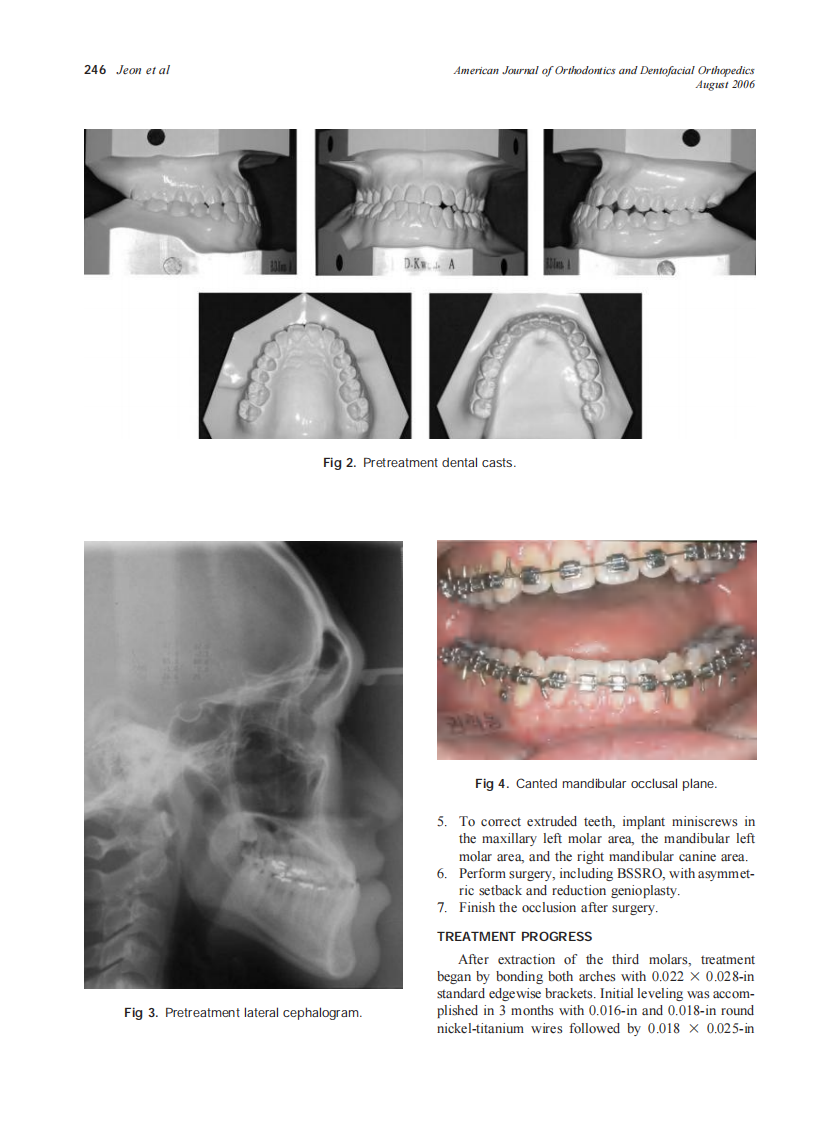

2006_130_2_244_252_Jeon.pdf